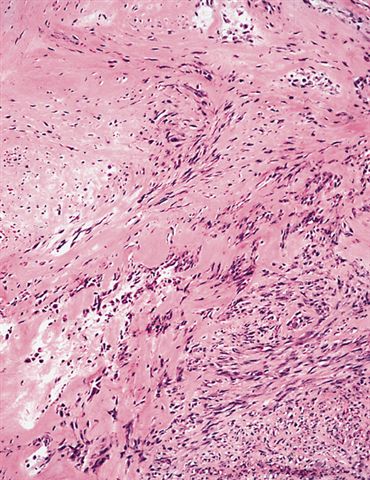

Microscopic (histologic) description

- Well circumscribed tumor of variable cellularity

- Cellularity mostly higher at tumor edges

- Bland spindle cells in a collagenous background

- Tumor has characteristic thin walled slit-like vessels

- Degenerative changes like myxoid / cystic change, osseous / chondroid metaplasia can be seen

- Bizarre pleomorphic cells can also be present

- Mitotically inactive

- Necrosis not present

- Cellular variant of fibroma of tendon sheath also exists; it overlaps morphologically with nodular fasciitis and fibrous histiocytoma (Cancer 1979;44:1945)

Microscopic (histologic) images

Contributed by Nasir Ud Din, M.B.B.S.

AFIP images